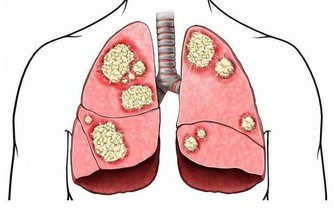

堅持讓他做個肺部CT,沒想到有肺部結節,進一步檢查確診原來是肺癌早期,

但是事實已經碰到好幾個病人檢查結果卻是肺內小結節,再進一步檢查原來是肺癌,

在過去的30年,我國肺癌死亡率上升了465%,

肺癌已經成為我國惡性腫瘤的第一位死亡原因,嚴重威脅大眾健康。

據統計,近50多年來,世界各國特別是工業發達國家,肺癌的發病率和病死率均迅速上升,

目前是全世界癌症死因的第一名,成為名副其實的“頭號殺手”。